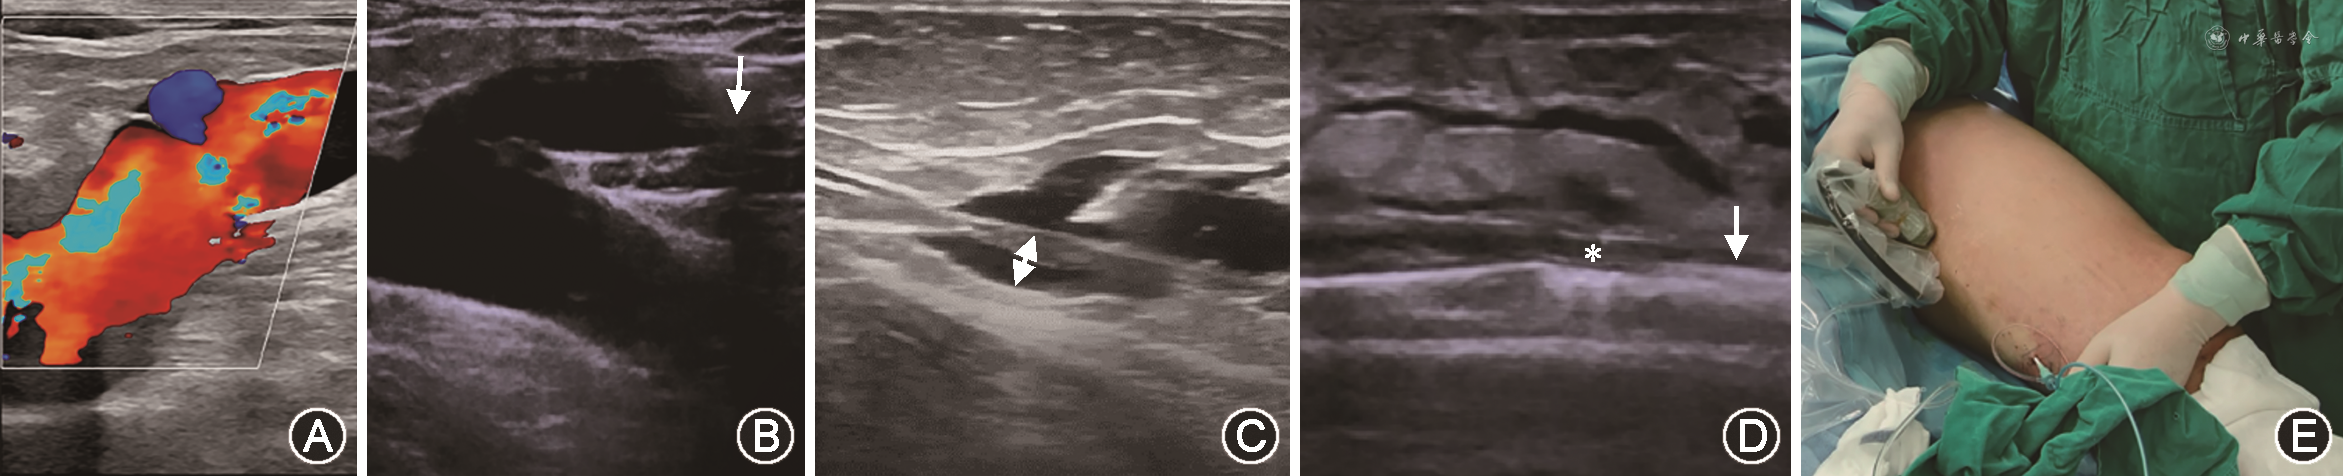

2. GSV主干微波消融闭合手术(图1):患者术区消毒铺巾,利用超声检查GSV全程后用穿刺针于超声引导下在患侧肢体大腿下段内侧GSV主干处穿刺,穿刺成功后置入7 F血管鞘。由7 F鞘内插入一次性水冷微波消融针(MTC-137),并向近心端上行至距离隐股静脉结合部2 cm处,超声引导下分段围绕GSV注射肿胀液,使周围液性暗区达到10 mm以上同时压闭GSV。再次确认微波消融针距隐股瓣膜开口约2 cm后开始微波消融闭合。打开微波治疗机,设定功率50 W,10 mm作为一个治疗点,脚控微波脉冲,缓缓后撤微波消融针,每点治疗时间3~4 s。消融针头部退至GSV穿刺点附近,则停止治疗,退出消融针。如若发现消融段GSV有流动血流则中转为GSV高位结扎、主干硬化剂注射术闭合GSV主干或激光消融闭合。